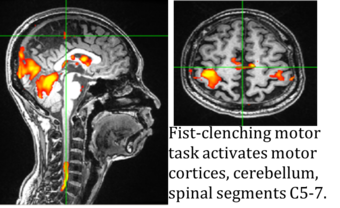

The Systems Neuroscience & Pain Laboratory at Stanford University (SNAPL) is actively recruiting a postdoctoral fellow who will join our research project on chronic pain. Funded by the National Institute of Health and directed by neuroscience professors Sean Mackey and Gary Glover, our goal is to investigate mechanisms of chronic pain using methods we developed to image the entire CNS via simultaneous spinal cord/brain fMRI.

Our plan is to characterize neurobiological mechanisms underlying chronic pain and use this information to develop objective biomarkers of pain, ultimately, to derive new personalized interventions. Given abundant findings that fMRI of the brain can act as biomarker for chronic pain conditions, we propose utilization of our simultaneous spinal cord/brain fMRI to develop biomarkers of pain severity. Our research can be categorized as follows: